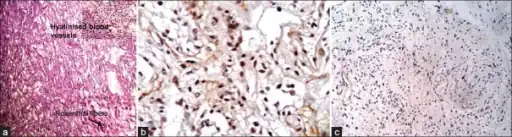

a-c) Photomicrograph shows microcystic areas in pilocytic astrocytoma

Histopathology of pilocytic astrocytoma (grade I WHO).

Under the microscope, the tumor is seen to be composed of bipolar cells with long "hair-like" GFAP-positive processes, giving the designation "pilocytic" (that is, made up of cells that look like fibers when viewed under a microscope[6]). Some pilocytic astrocytomas may be more fibrillary and dense in composition. The presence of Rosenthal fibers,[7] eosinophilic granular bodies, and microcysts can often be seen. Myxoid foci and oligodendroglioma-like cells may also be present, though these are not specific to pilocytic astrocytoma. Long-standing lesions may show hemosiderin-laden macrophages and calcifications.